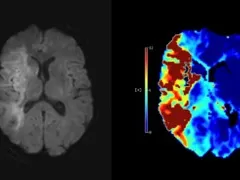

This fellowship course provides deep insights into the ischemic stroke MRI findings. You will learn to optimize and execute the MRI brain stroke protocol, covering essential sequences for identifying ischemic changes and infarcts.

This training focuses on a practical approach to managing stroke patients in your radiology workflow using MRI. There will be an emphasis on how to extract as much information as you can from your basic sequences as well as how this correlates with more advanced imaging like perfusion.

It will encompass both the basic aspects of MRI interpretation, but also in part focus on which findings are important to underline for patients who need mechanical thrombectomy and how to communicate these to your colleagues to optimize the stroke workflow.

- Recognize infarcted and tissue at risk

- How to localize thrombus and indirect signs of penumbra